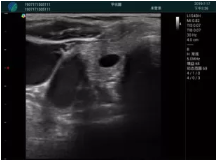

M20查看:囊內回聲均勻,邊界清晰,囊壁光滑

M20引導抽吸術后囊腫消失,原區(qū)域空腔形成,脂肪層與腺體層架構發(fā)生改變